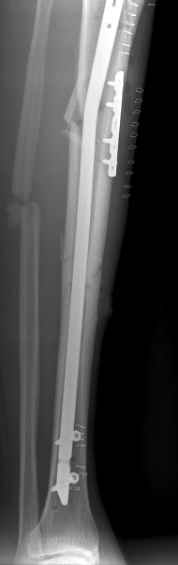

These can be challenging. I agree w/ all Dr. Carr's points. My preference to prevent the deformity is to use an anteromedial plate. See attached case.